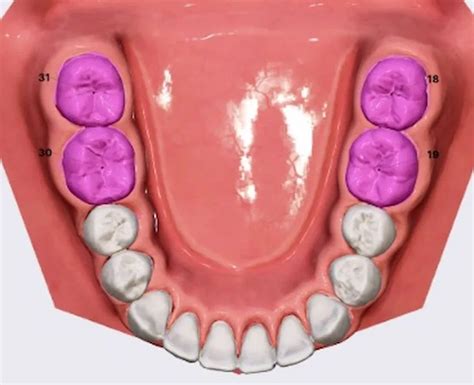

Fig. 17. Como consecuencia de la posición de reposo patológica de la lengua surgió una protrusión con grandes espacios interdentales y mordida cruzada frontal, a vista oclusal y b frontal.